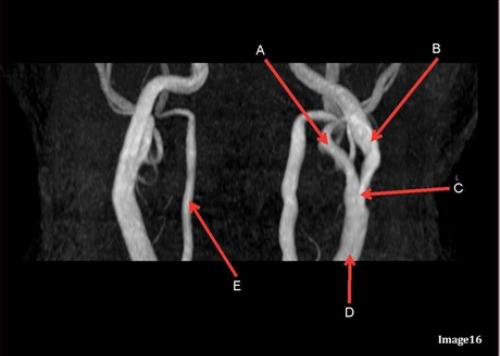

Letter A in Image 16 is responsible for blood supply to the:

A. Anterior brain

B. Posterior brain

C. Face

D. Upper extremities

Letter D in Image 16 is pointing to:

A. Internal carotid artery

B. External carotid artery

C. Vertebral artery

D. Common carotid artery

E. Common carotid bifurcation

Image 16 is an example of what type of MR image?

A. MR Spectroscopy

B. MRA Circle of Willis

C. MRV intracranial circulation

D. MRA extracranial circulation

E. MRA intracranial circulation

Letter E in Image 16 is responsible for blood supply to the:

Letter B in Image 16 is responsible for blood supply to the:

Letter A in Image 16 is pointing to:

Letter B in Image 16 is pointing to:

Letter C in Image 16 is pointing to:

Letter E in Image 16 is pointing to: